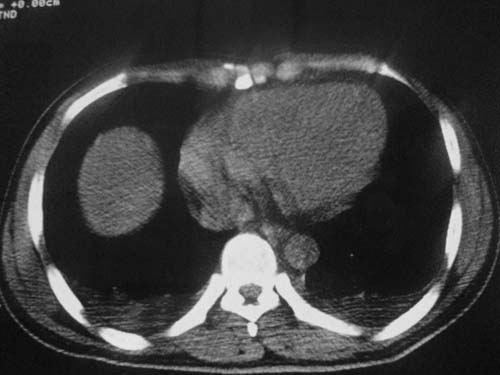

这是第五天拍的ct,纵隔窗我没都传,实在是太费时,请教各位老师,此病人有肺水肿吗?帮忙分析一下

不知道具体外伤的情况(部位,方式‘程度等),肺内病变范围较广,上下叶都有,似乎与肺挫伤不相符合,是应该看看临床治疗详情,特别是输液出入量,以前见过类似的病人,间质性肺水肿可能大!等待结果,盼盼盼!

跟主治医生讨论病例

结果:病人刚入院水电解质紊乱,治疗期间大量输液,而且速度较快,正如4.5楼那样说的引起肺水肿,对症治疗后病情好转,